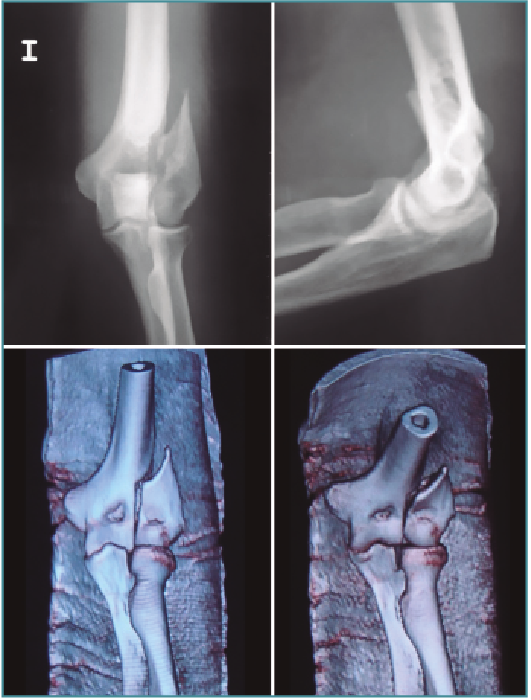

Fractura supraintercondílea del húmero

Las fracturas supracondíleas también requieren una reconstrucción con tornillos y placas, y una artrotomía en la mayoría de los casos. Las fracturas supracondíleas se dividen en 2 tipos: en extensión (la mayoría) y en flexión.

Las fracturas que se presentan con una mínima inflamación son susceptibles de fijación artroscópica asistida. El hematoma y los restos articulares se eliminarán y usaremos una o varias AK para reducir la fractura percutáneamente (Figuras 9 a 12) colocando a continuación tornillos canulados en la columnas medial o lateral del húmero. Se debe usar el fluoroscopio para evitar introducirlo dentro de la fosa olecraniana(11).

Figura 9. Radiografías y tomografía axial computarizada de fractura supraintercondílea.

Figura 10. Colocación del paciente, visión articular de la fractura y reducción artroscópica.

Figura 11. Fijación interna con 3 tornillos canulados, control por escopia y artroscópica.

Figura 12. Resultado final.

En el postoperatorio, los pacientes pueden comenzar ejercicios de rango de movimiento protegidos de manera inmediata y así reducir las posibilidades de rigidez postoperatoria asociadas con el tratamiento cerrado de estas fracturas(12).